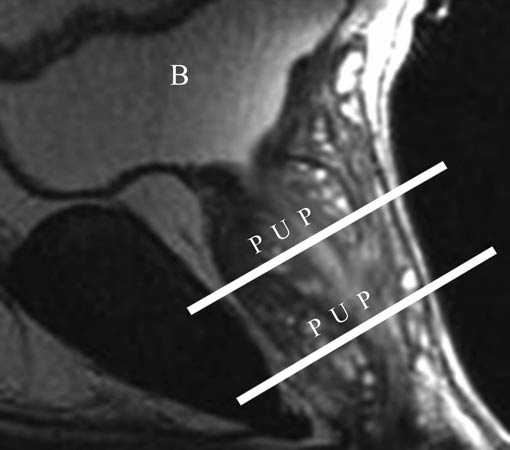

Imagen por RMN a través del centro de la pelvis de un hombre vista desde el costado. La vejiga (B) se ve en la parte superior de la imagen.

P = Prostate

U = Uretra